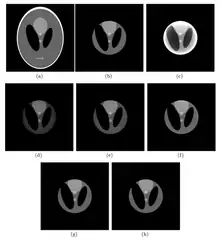

The first interior-reconstruction method listed below is extrapolation. It is a local tomography method which eliminates truncation artifacts but introduces another type of artifact: a bowl effect. An improvement is known as the adaptive extrapolation method, although the iterative extrapolation method below also improves reconstruction results. In some cases, the exact reconstruction can be found for the interior reconstruction. The local inverse method below modifies the local tomography method, and may improve the reconstruction result of the local tomography; the iterative reconstruction method can be applied to interior reconstruction. Among the above methods, extrapolation is often applied.